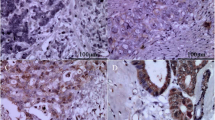

We analyzed the expression of CCR7 in 42 clinical samples from gallbladder cancer patients and 22 normal gallbladder tissues adjacent to the carcinoma using immunohistochemistry. CCR7 was detected in the cytoplasm and membrane of GBC cells (Fig. 1b–d). However, negative or low levels of CCR7 expression were observed in the adjacent tissues. As shown in Table 2, CCR7 was expressed in 90.47 % (38/42) of GBC samples, which was significantly higher than that of adjacent tissues (22.73 %) (P < 0.05).

Fig. 1 Table 2 The expression of CCR7 in the specimens of GBC and adjacent tissues The relationship between CCR7 expression and select clinicopathologic factors is shown in Table 3. Higher expression (+++ to ++++, strong staining) of CCR7 was associated with AJCC staging (I-IIa vs IIb-IV, P = 0.008 < 0.05) and lymph node metastasis (negative vs positive, P = 0.003 < 0.05), but not with age, gender, histological grade, and classification. Taken together, CCR7 overexpression may be involved in the lymph node metastasis of gallbladder cancer.